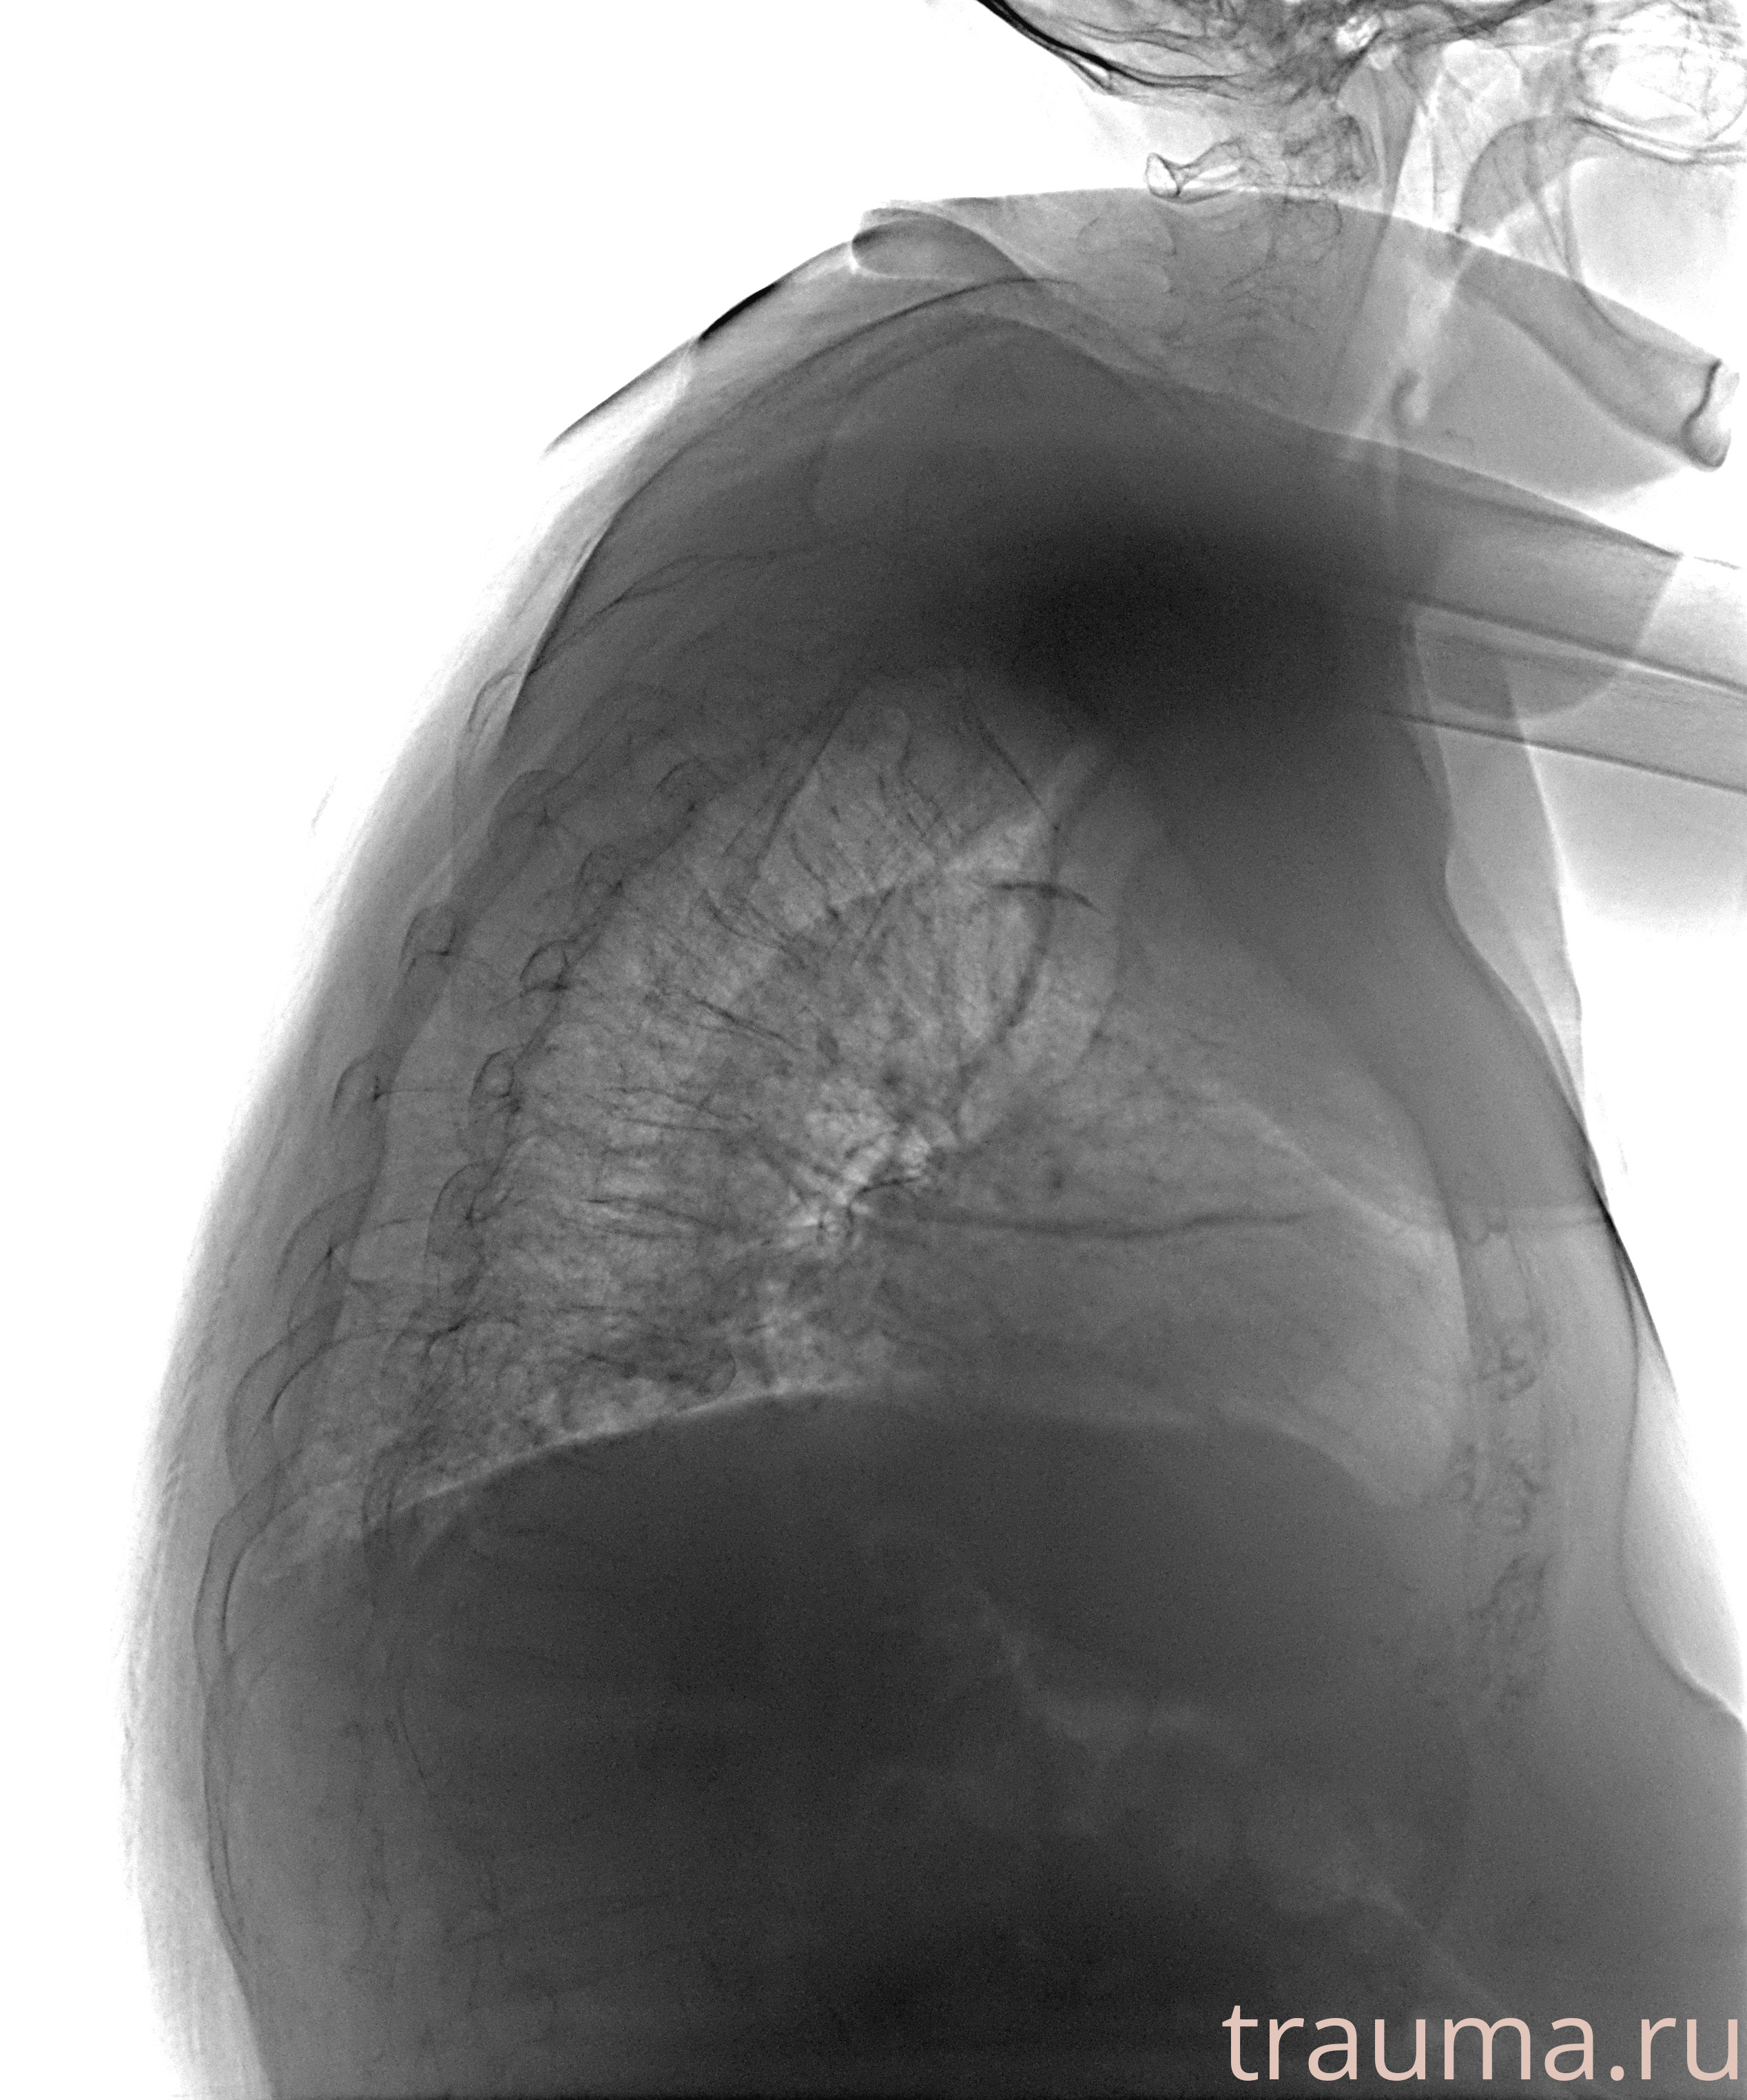

Перелом 3-5 ребер слева